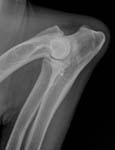

Gesundheitsstatus vom 26.11.2018 Die Röntgenbilder zeigen keinen Hinweis auf HD oder ED bei Lena vom Gehrensee. Die veterinärmedizinischen Untersuchungen von Jana auf HD, ED u. DCM und die Zuchtzulassungsprüfung wurden erfolgreich bestanden.

Die Gelenke sind HD und ED - frei, das Herz ohne Befund. Vor dem Hintergrund, dass seit 5 Generationen alle Zuchthündinnen bis ins hohe